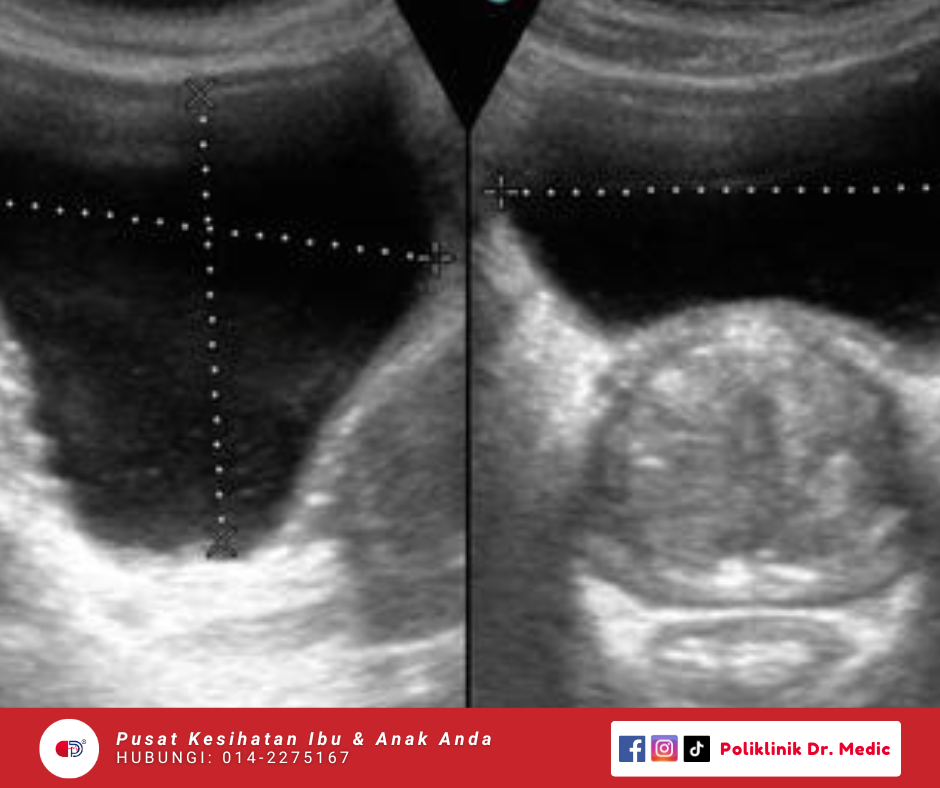

scrotal + KUB + Prostate

Pemeriksaan untuk testis, saluran sperma, buah pinggang, saluran kencing dan prostat bagi mengenal pasti punca masalah kesihatan lelaki. Pemeriksaan ini membantu mengesan awal keadaan seperti ketulan, varikokel (urat membesar), jangkitan, batu karang, penyakit buah pinggang.

RM160